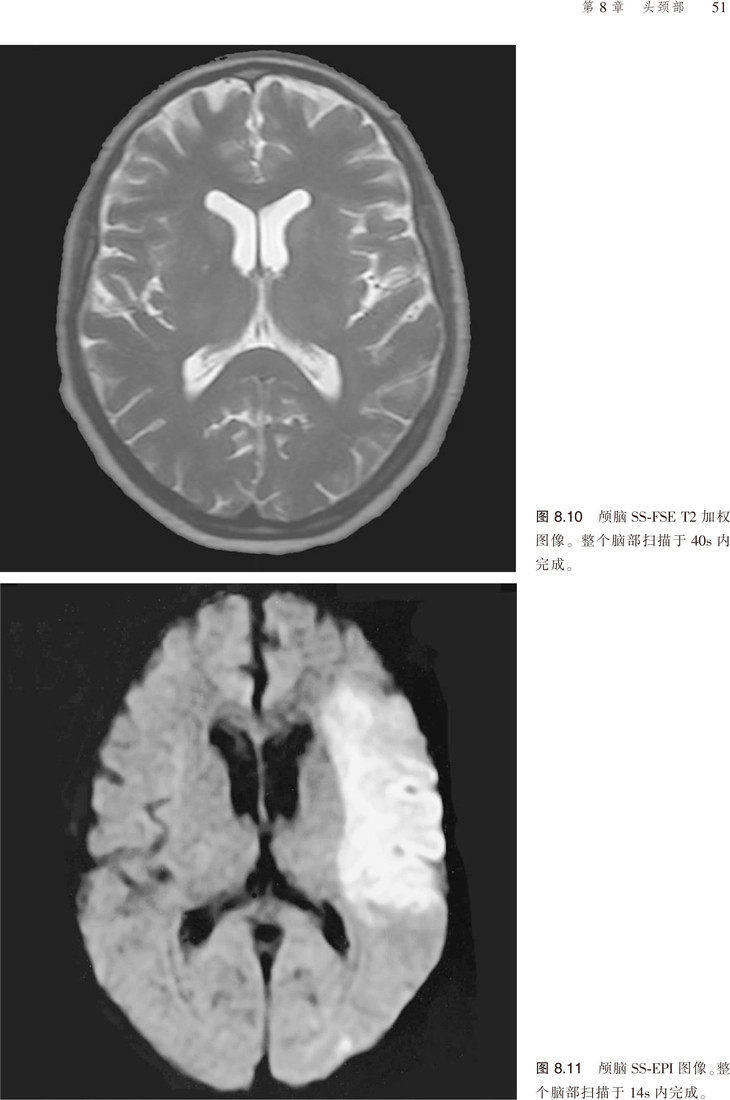

该书对脉冲序列、伪影、门控技术、预饱和技术等原理进行了讲解,且涵盖临床应用的相关参数,并就对比剂等以及受检者的安全性进行了分析。更为可贵的是该书不仅有应用解剖图谱,还有扫描的参照图,便于读者阅读,加深对书中内容的理解。